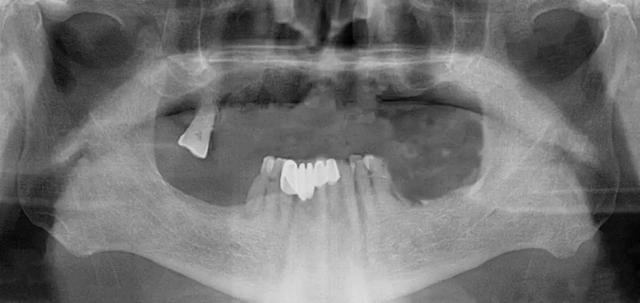

家住安丘的郎先生,因上牙床僅剩一顆牙齒,吃飯很受影響。在了解到濰坊市中醫(yī)院口腔科種植全口牙當(dāng)天可以接著戴牙吃飯,慕名來找李德仁主任尋求幫助。

口腔科李德仁主任為老人仔細(xì)檢查了口腔情況,由于缺牙時間太久,牙床骨量極少,正常的種植修復(fù)需要植骨,手術(shù)創(chuàng)傷大而且半年后才能鑲牙吃飯。建議他進(jìn)行數(shù)字化導(dǎo)板種植,可以不用植骨而且當(dāng)天就能戴牙吃飯,手術(shù)簡單,創(chuàng)傷小。老人和孩子很信任的接受了李主任的種植方案:上牙床種植5顆,下牙床種植4顆,當(dāng)天戴牙吃飯。